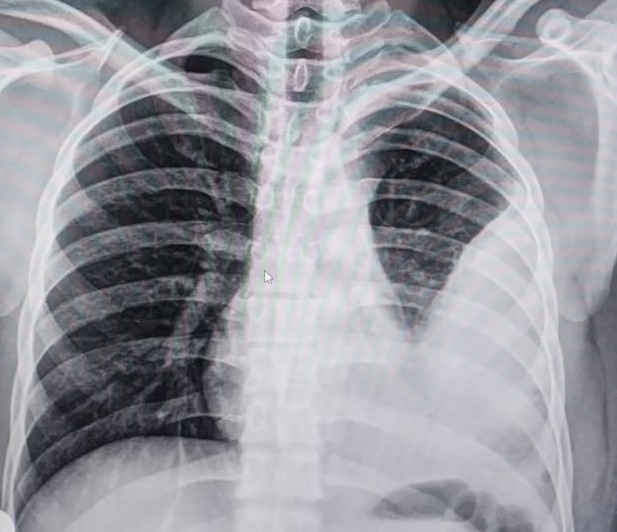

draurtecho Ago 27, 2024 Las técnicas de diagnóstico por imágenes son fundamentales para el diagnóstico de la enfermedad pulmonar. Las radiografías de tórax, las ecografías pulmonares y las tomografías computarizadas ofrecen ventajas y limitaciones únicas. Reconocer patrones radiológicos específicos es útil para identificar patógenos y orientar el tratamiento. No Comments InNeumología